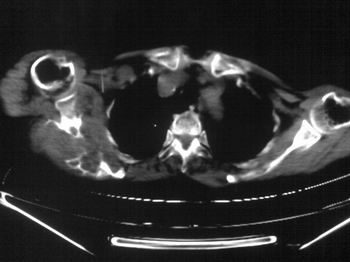

以下是引用zhangxu5888在2007-9-11 16:25:00的发言:[br]有侧肩胛骨溶骨性破坏且见软组织成分,增强软组织强化明显,中央见低密度坏死区!根据病史10年,考虑良性肿瘤恶性变!性质待定!

以下是引用老爱克斯新网客在2007-9-11 18:22:00的发言:[br]应该是良性肿瘤恶变,但因晚期破坏严重不能见到原来肿瘤征象无法判断,